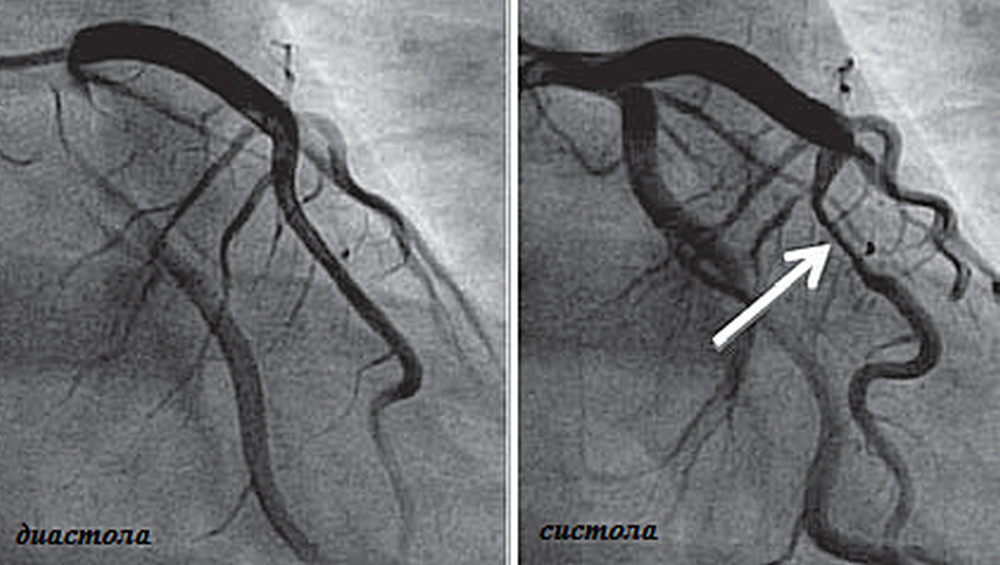

Анатомия коронарных артерий: КТ-изображения

Раздел: Снимки успеха